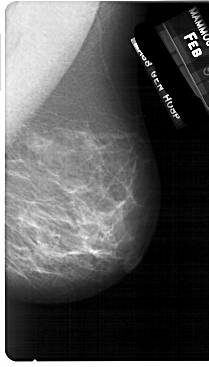

A_1710_1.RIGHT_MLO

RIGHT_MLO LINES 5491 PIXELS_PER_LINE 3121 BITS_PER_PIXEL 12 RESOLUTION 43.5 NON_OVERLAY